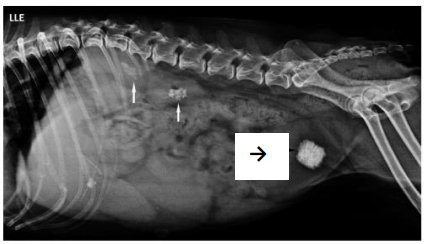

Foi solicitada uma radiografia látero-lateral esquerda do abdome,

permitindo identificar três pontos indicados na imagem abaixo:

duas setas brancas e uma preta.

As setas brancas e a seta preta mostravam, respectivamente,